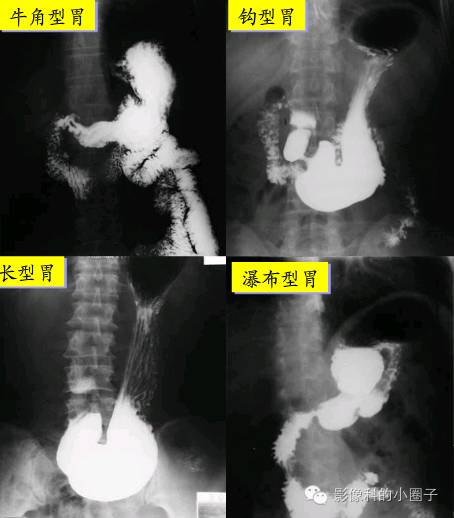

牛角型胃多见于肥胖体型人:钩型胃是最常见的类型;长型胃又称无力型胃

长型胃(无力型):瘦长体型,张力低,上窄下宽,犹如水袋,胃下极低于髂嵴

– 分型:牛角型,中间型,瀑布型,无力型 – 分部:贲门,胃底,胃体,胃窦

又名无力型胃,呈垂直位,外观如水袋形状,多见于消瘦人群.